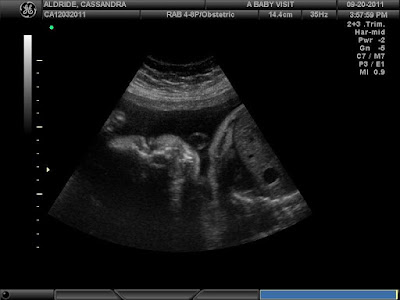

September 20, 2011: Jake and I drove out to Riverside for our 3D ultrasound. We were almost sent home with a return appointment, since Jayden did not want to co-operate! He had his feet up over his head and his hands in front of his face. Eventually, the tech was able to wake him up and we got to see our sleepy boy! :) This was a happy distraction from the devastating news we had just gotten.